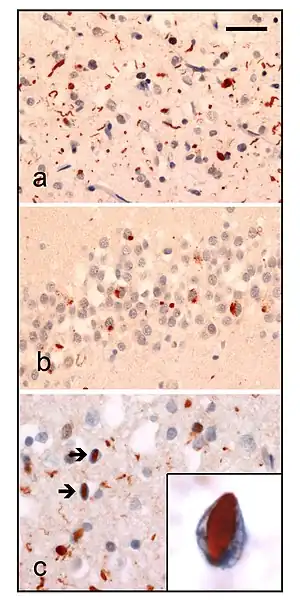

| Neuropathologic analysis of brain tissue from FTLD-TDP patients. Ubiquitin immunohistochemistry in cases of familial FTLD-TDP demonstrates staining of (a) neurites and neuronal cytoplasmic inclusions in the superficial cerebral neocortex, (b) neuronal cytoplasmic inclusions in hippocampal dentate granule cells, and (c) neuronal intranuclear inclusions in the cerebral neocortex (arrows). Scale bar; (a) and (b) 40 μm, (c) 25 μm, insert 6 μm. | |